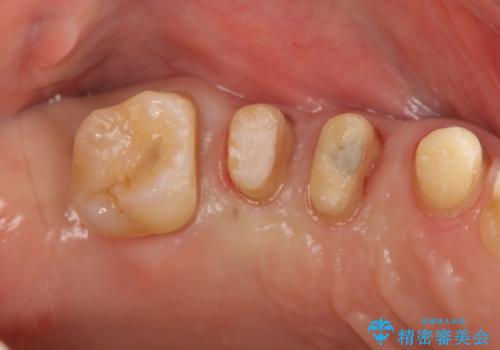

検査の結果、強い歯ぎしりによる歯の周囲の骨の吸収が認められたため歯槽骨の再生・歯周ポケットの除去・力に対抗する連結補綴・補綴前処置としての小矯正を計画します。

今回連結補綴を行うにあたり、歯周病の問題を解決するために再生療法・歯周ポケット除去手術を、またより歯の神経を保存し力に対抗できる環境を整えるために小矯正を行い精度の高いメタルボンドクラウンを製作することができました。